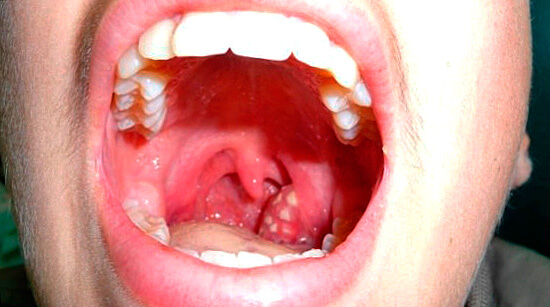

شرح بالصور لـ جميع انواع التهاب اللوزتين المرسال

سرطان اللوزتين

التهاب اللوزتين المزمن والتهاب اللوزتين الأسباب والأعراض وطرق العلاج الطبي ومراحل التصوير من المرض

ما هي الأعراض الرئيسية لالتهاب اللوزتين ومتى يكون خطيرا يمن مونيتور